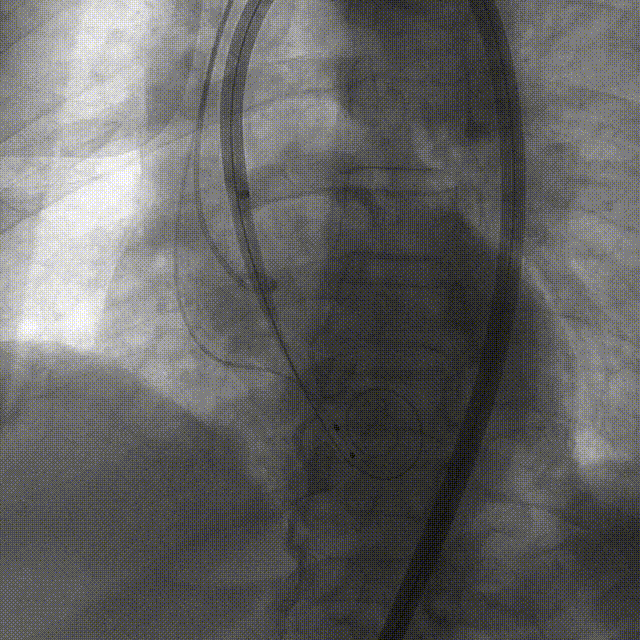

手术过程:5A 标准化流程SOP

术前右窦中心造影

大鞘植入